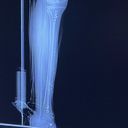

As a result of this senseless act, JB has had 3 surgery’s while suffering a broken leg, two torn arteries, and significant trauma to his body and also have a rod In his left leg. Thirty staples were placed in his left leg, twelve in his left knee, and additional staples behind his head. The road to recovery will be long and painful, with numerous surgeries, physical therapy, and an uncertain future ahead. JB will be unable to work for an unknown period of time, and the financial strain is already beginning to weigh heavily on him.